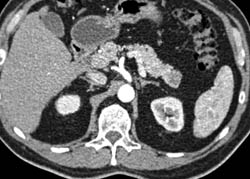

Chronic Pancreatitis